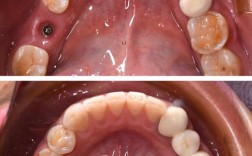

微创拔牙与种植体植入

- 微创拔牙:使用微创拔牙器械(如挺子、超声骨刀),尽量保留唇侧骨板的完整性,避免暴力操作导致骨裂;

- 种植窝预备:根据数字化导板方向,逐级备洞,注意控制温度(<47℃),避免骨灼伤;

- 植入种植体:选择直径≥3.5mm、长度≥10mm的亲水性表面种植体(如Straumann SLActive、NobelActive),确保初期稳定性≥35Ncm(用扭矩扳手检测),种植体顶端应位于牙槽嵴下1-2mm,为临时修复体留出空间。

骨增量与软组织处理(必要时)

若唇侧骨板厚度<2mm或存在缺损,可联合引导骨再生技术(GBR):植入骨粉(如Bio-Oss)覆盖骨缺损区,覆盖可吸收生物膜(如CollaTape),防止软组织长入,促进骨再生,牙龈需无张力缝合,避免血供不足导致坏死。

临时修复体制作与戴入

- 取模:若种植体初期稳定,可即刻取模(使用硅橡胶或树脂类材料);若稳定性不足,可延迟3-7天取模;

- 制作临时冠:在技工室制作树脂临时冠,形态、颜色尽量与邻牙一致,穿龈部分模拟自然牙龈轮廓,避免压迫牙龈;

- 戴入与调𬌗:临时冠粘接后,调整咬合,确保无早接触、无干扰,避免种植体承受过大咬合力。